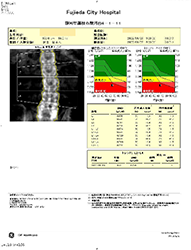

骨密度測定 【3,960円】

腰椎(腰の骨)の骨密度をX線を用いて測定します。骨密度が低下すると腰椎の圧迫骨折の原因となることがあります。仰向けで寝たまま5分くらいで検査できます。